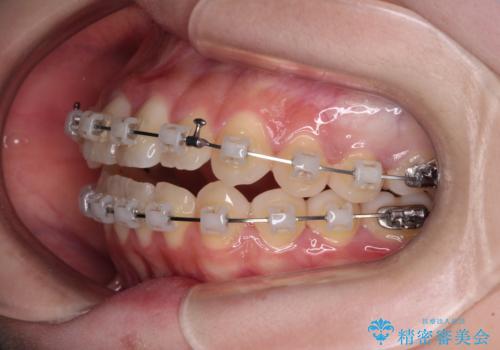

- クリアブラケット

- 前歯のデコボコと非接触の上下前歯を気にして来院された患者様です。

上下前歯の隙間は舌の突出癖によるもので、隙間改善のためには舌のトレーニングがとても重要となります。

口元の突出感はないため、抜歯矯正の適用ではありませんが、デコボコを解消する際に外側に拡大されてしまうと治療前と比べて出っ歯になった印象にもなるため、舌の突出癖の改善が必須となります。

インビザラインによる治療は自己管理が煩わしいとのことで、ワイヤー装置による矯正治療を行うこととしました。

治療開始当初は舌の突出癖が改善されておらず、上下前歯の隙間がより顕著な状態となりました。